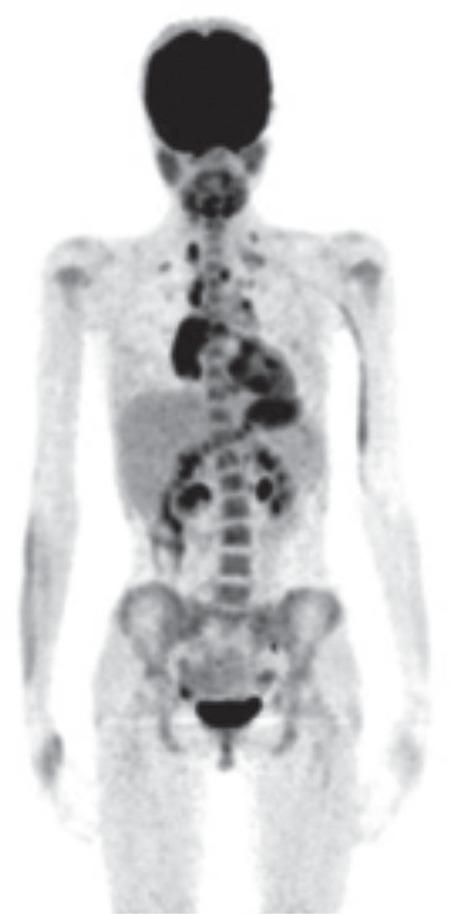

小儿霍奇金淋巴瘤治疗前氟脱氧葡萄糖正电子发射断层扫描/计算机断层扫描参数与临床预后因素的相关性

The Correlation Between Pre-treatment Fluorodeoxyglucose Positron Emission Tomography/Computed Tomography Parameters and Clinical Prognostic Factors in Pediatric Hodgkin Lymphoma.

To compare standardized uptake values (SUV) derived from pre-treatment F-fluorodeoxyglucose (FDG) positron emission tomography/computed tomography (PET/CT) imaging and clinical prognostic factors in pediatric patients with Hodgkin lymphoma (HL).

METHODS

Pre-treatment FDG PET/CT findings of 28 children with HL were evaluated in this retrospective study. Metabolic tumor volume (MTV), SUV normalized by weight (SUV), lean body mass (SUV), body surface area (SUV) and plasma glucose levels of tumors (SUV) were calculated using pre-treatment FDG PET/CT scan images. These metabolic parameters were correlated with clinical factors [age, sex, number of lymph node groups, presence of splenic involvement, bulky mediastinal disease, Ann Arbor stage, serum white blood cell (WBC) count, erythrocyte sedimentation rate (ESR), serum albumin and hemoglobin levels].

RESULTS

SUV, SUV, SUV, SUV and MTV were higher in patients with stage III-IV disease, bulky tumor and ≥3 lymph node groups (p<0.05). SUV and SUV were higher in patients with splenic involvement (p<0.05). There was no significant correlation between these metabolic parameters and sex, ESR, levels of albumin and WBC (p>0.05). SUV and SUV were higher in patients with anemia (p<0.05). Additionally, significant increases were detected in SUV, MTV, and SUV with increasing age (p=0.005, p=0.027, and p=0.009, respectively). SUV and SUV had no significant correlation with age (p>0.05).

CONCLUSION

Metabolic parameters derived from pre-treatment FDG PET/CT may have an important role in predicting high-risk disease in patients with HL. Also, SUV and SUV may be better markers than SUV in the quantitative evaluation of FDG PET/CT scans in pediatric patients.